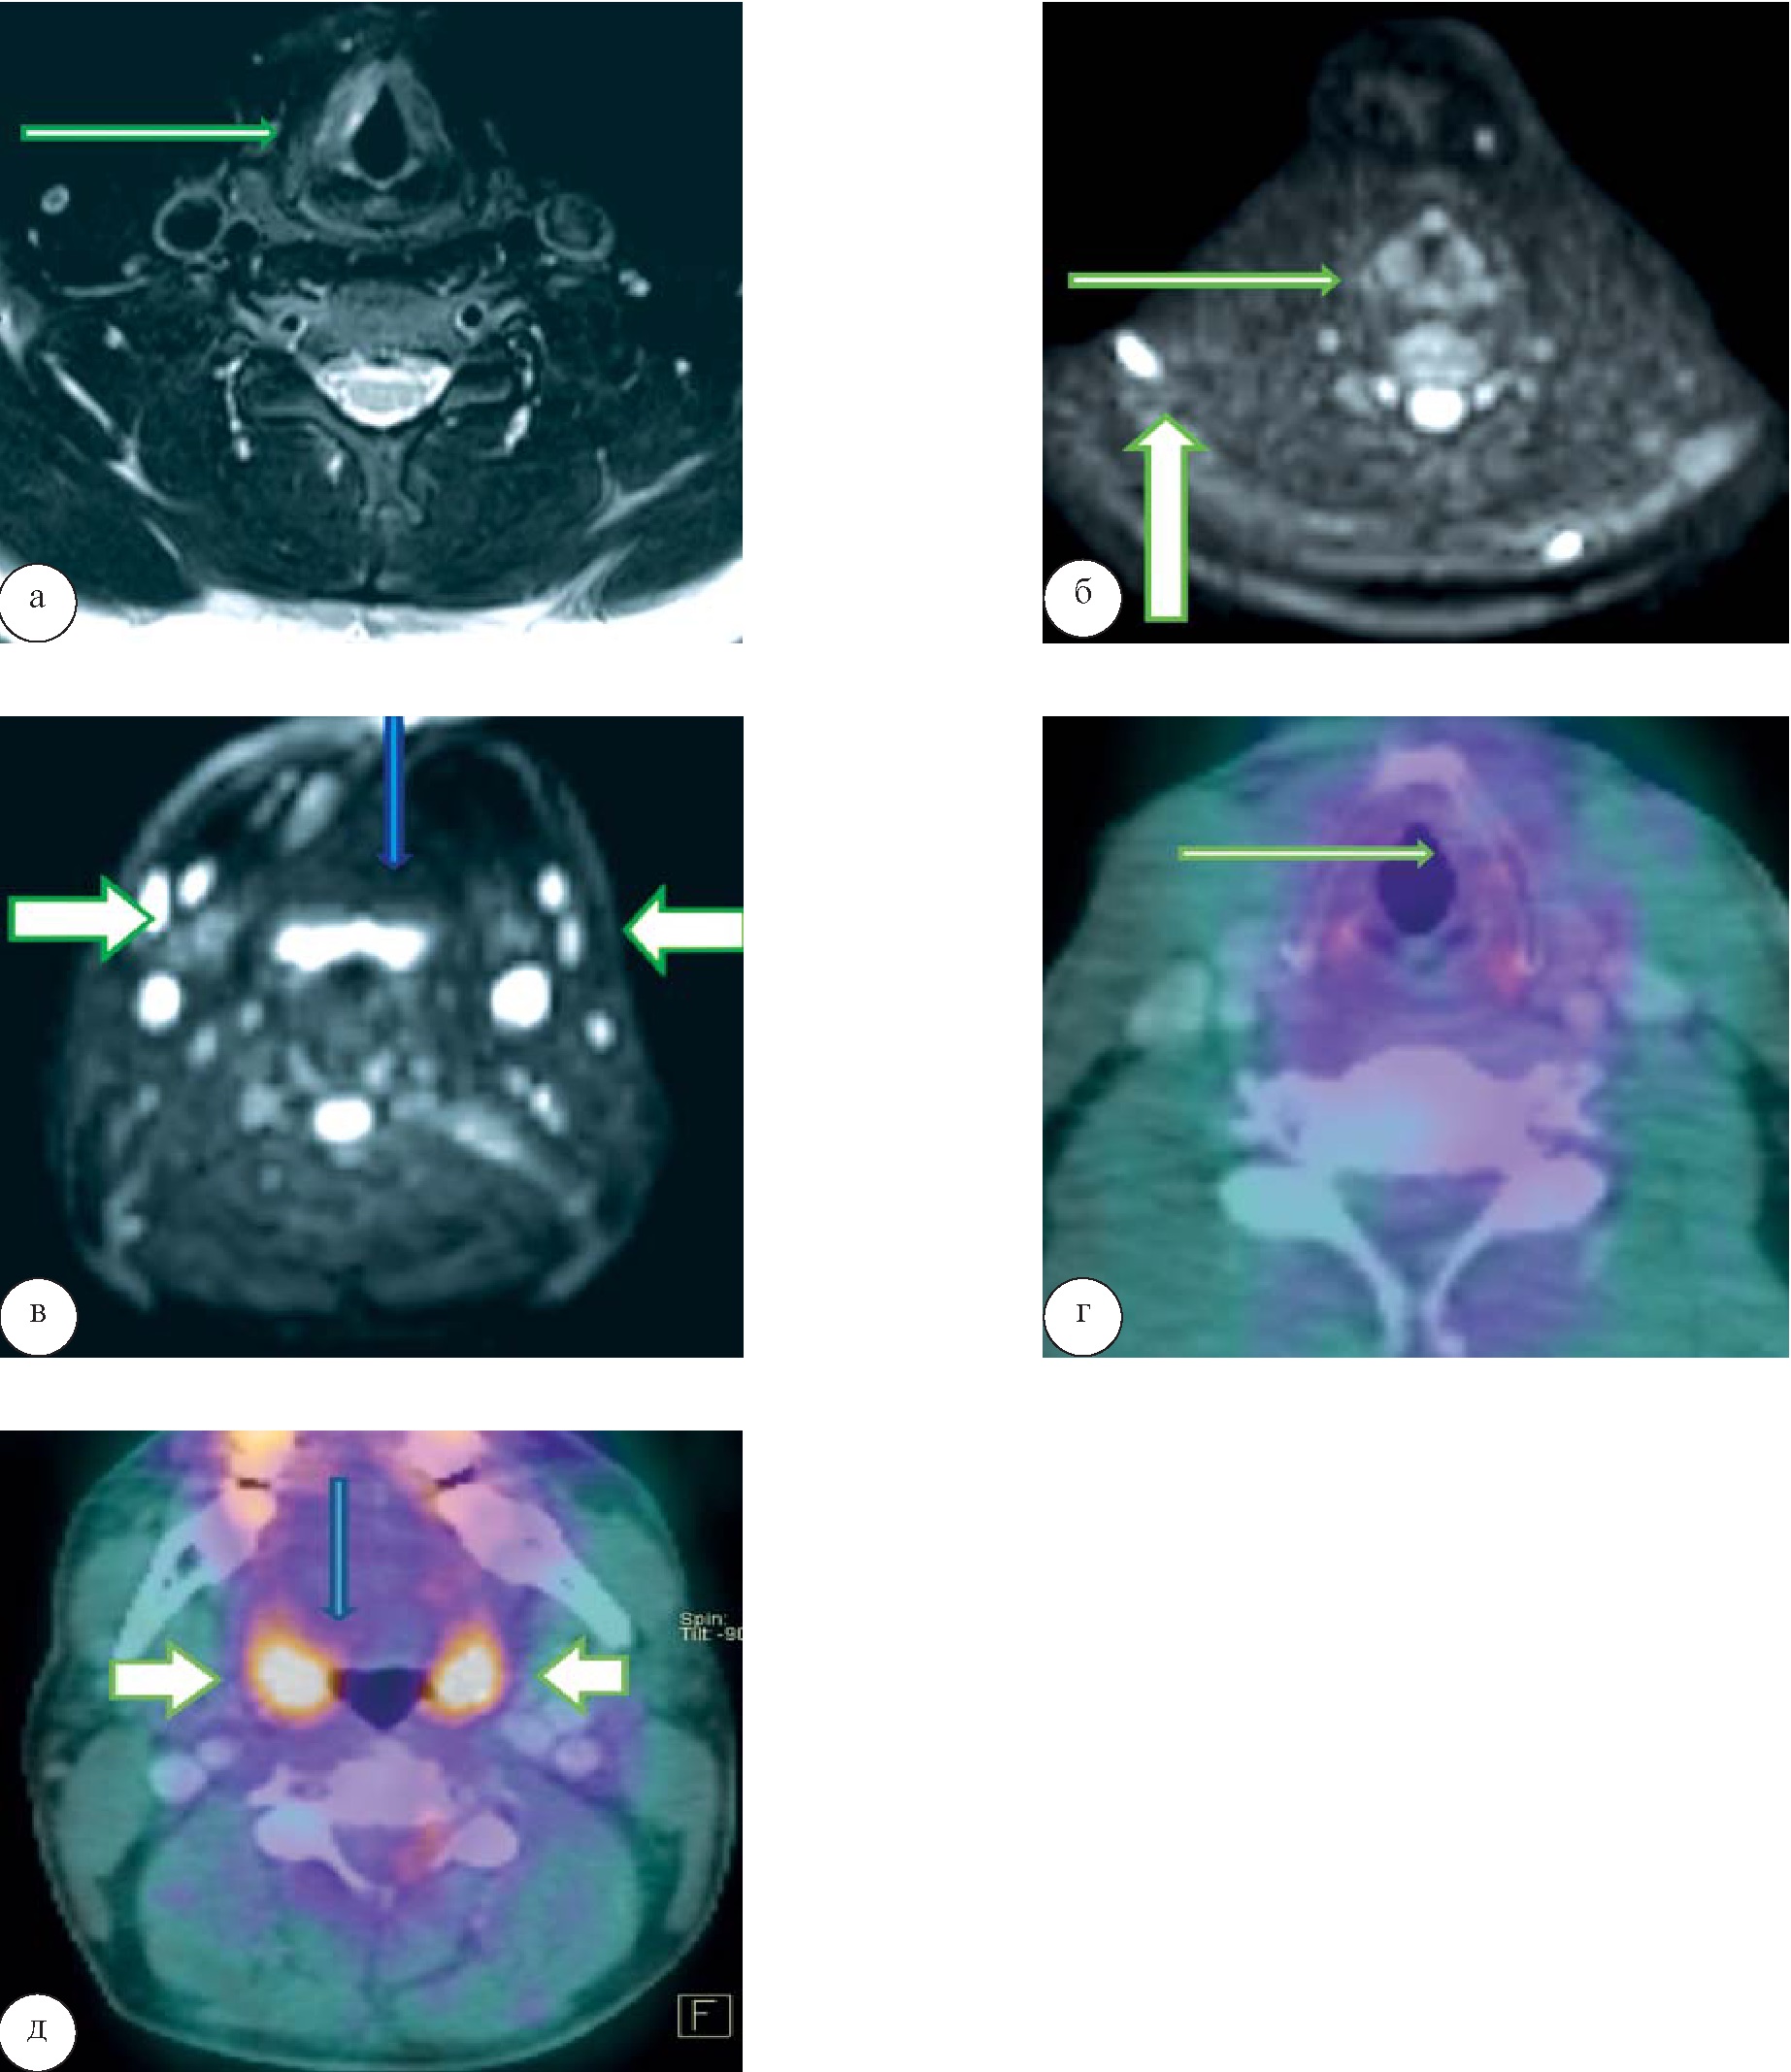

У 3 человек (5,5%) гиперметаболизма ФДГ в области образований не выявлено, в области лимфатических узлов прослеживался небольшой уровень захвата РФП (SUVmax 2,6), что трактовалось как реактивные воспалительные изменения лимфатических узлов (рис. 5). Воспалительную природу увеличенных шейных лимфатических узлов подтверждало увеличение небных и глоточной миндалин с повышенным уровнем метаболизма глюкозы (SUVmax 5,1).

Рис. 5. Воспалительные изменения правой голосовой складки. При МРТ на Т2-ВИ определяется гиперинтенсивное образование правой голосовой складки (а), характеризующееся отсутствием повышенного сигнала на ДВИ (тонкая белая стрелка) с визуализацией повышенного сигнала в области множественных лимфатических узлов Ia, Ib, IIa, IIb, III, Va групп с обеих сторон (б, в) (толстые стрелки) и в области лимфоидного кольца Пирогова – Вальдейера (голубая стрелка). На ПЭТ/КТ-изображениях (г, д) гиперметаболизма глюкозы в области образования правой голосовой складки не прослеживается (тонкая белая стрелка), в области шейных лимфатических узлов прослеживается небольшой уровень захвата РФП (толстые д стрелки) и повышенный уровень захвата воспалительного характера в области миндалин (голубая стрелка)